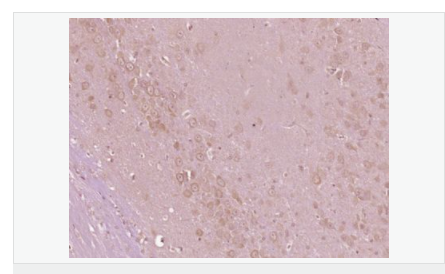

交叉反應:Mouse,Rat(predicted:Human,Dog,Pig,Horse,Rabbit) 推薦應用:IHC-P,IHC-F,IF,ELISA

產品應用ELISA=1:5000-10000 IHC-P=1:100-500 IHC-F=1:100-500 IF=1:100-500 (石蠟切片需做抗原修復)

image.png